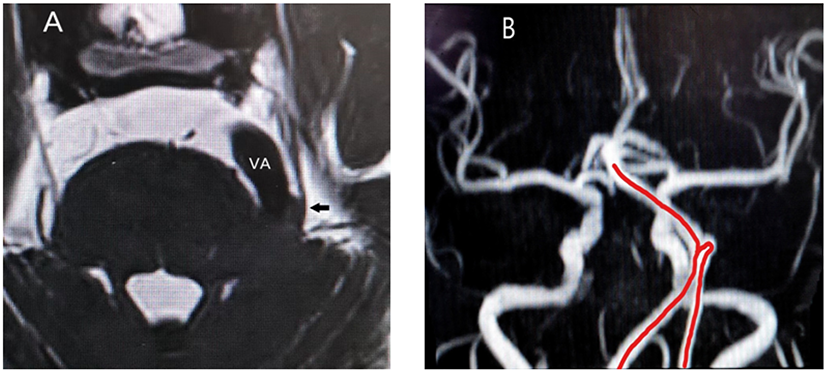

The occurrence and development of CTN involve many conditions, and it is a progressive process that has serious negative physiological and psychological impacts on the patients. NVC and the subsequent pathological changes caused by NVC, such as nerve ischemia, demyelination, and compensatory changes of the CNS in response to chronic pain, may be involved in the course of TN. MVD is currently the best surgical treatment, and its choice should rely on preoperative MRI examination, as none of the clinical features can differentiate between the three types of TN. Moreover, since the surgical field of vision is focal, it is impossible to observe the impact of the vascular motion amplitude after effective decompression, while magnetic resonance angiography can fully reveal the overall direction of the responsible vessels before surgery (Figure 3), so that the surgeon can fully prepare.

Figure 3

(A) Relationship between trigeminal nerve and responsible vessel in a patient on sequences-3D-SPACE; VA, vertebral artery; arrow, trigeminal nerve; (B) The red line is the abnormal routing of vertebral artery on magnetic resonance angiography.